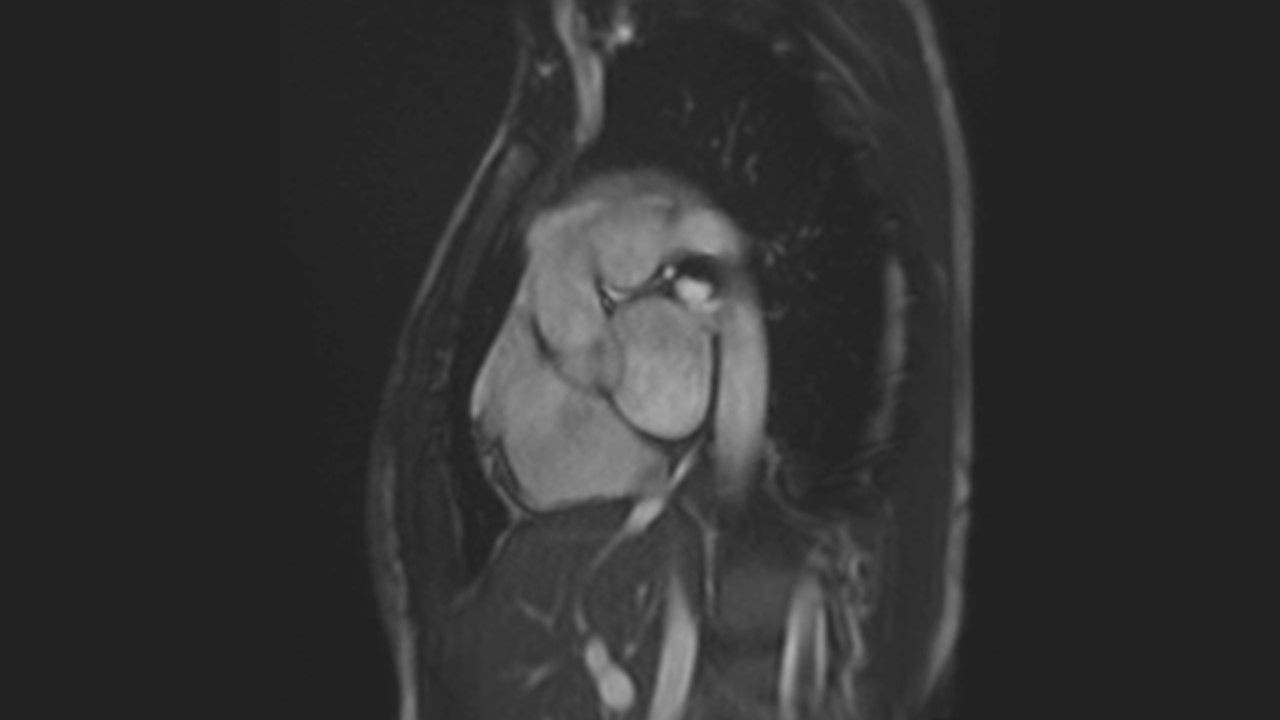

3 Chamber View